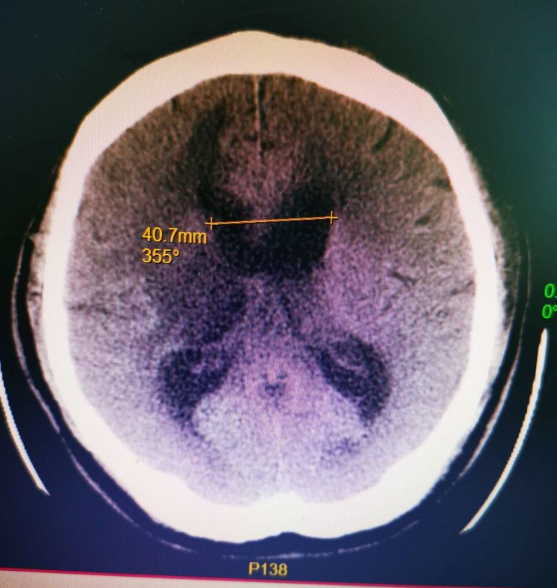

▲术后第二天影像

在福建医科大学附属第一医院江常震教授的指导下,郭协力副院长、齐震主任、陈晓海副主任医师及蔡明发主治医师等人通力合作,于7月22日对王先生进行了微创神经内镜三脑室底造瘘术。手术利用脑室镜微创进入第三脑室,开放第三脑室底部约5mm,再造脑脊液循环通路,使脑室内积水得以流出。手术用时1个多小时就顺利完成,术后患者恢复到患病前状态,脑积水症状及影像均有不同程度的好转。

神经内镜技术是微创神经外科的一门新兴技术,它的微创理念符合目前神经外科发展趋势,减少了患者的创伤,促进患者的恢复。该手术方式较传统的脑室腹腔分流术减少了长期体内留置分流管及容易逆行感染堵管等风险、并且从患者思想解除了长期置管的压力。该项手术的成功实施也标志着晋江市医院神经外科神经内镜方向正逐渐成长成熟。